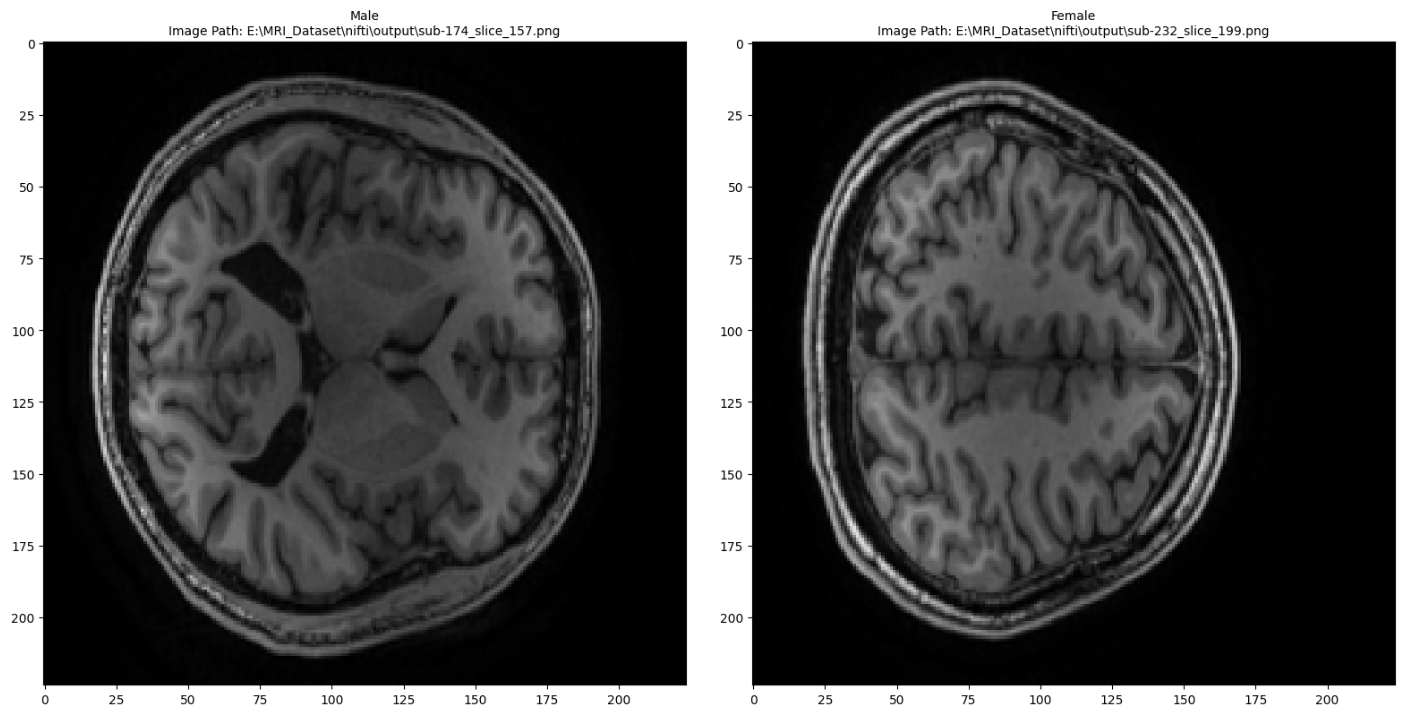

This dataset contains images of brain MRI scans of 301 healthy adults (181 younger, 120 older adults) alongside information about their sex, age and education. It contains 30 images from the coronal axis of each person's scan. It was created using the Neurocognitive aging data release with behavioral, structural, and multi-echo functional MRI measures dataset, created by Spreng et al..

An example on how this dataset can be used for predicting the gender using a simple CNN can be found here: MRI Gender Classification.